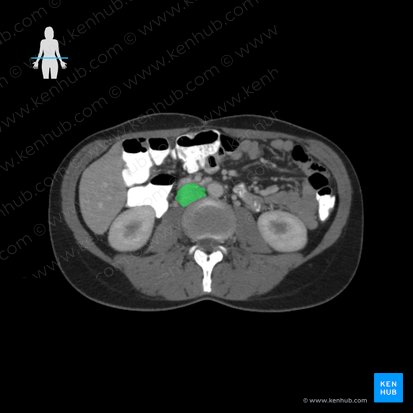

How to read an abdominal CT

Computed tomography (CT or CAT scan) is one of the most commonly used medical imaging procedures in clinical practice, along with radiography (x-ray) and magnetic resonance imaging (MRI). When the pathological process in the abdominal cavity is suspected, the x-ray and CT scans are the methods of choice because they are fast, cheap, widely available, non-invasive and they can be performed without special preparations of the patient.

CT is an imaging technique that uses x-ray beams to produce images that depict the tissues in two and three dimensions based on their density. The density of the structures is expressed in the Hounsfield unit (HUs) and it reflects the level of absorption of x-ray beams by certain structures in the body. It ranges from +1000 (hyperdense), 0 (isodense), to -1000 (hypodense).

Before getting into the detailed description of the structures that are visible on the abdominal CT, it is important to know how to orientate with a CT scan. The axial scans (cross-sectional images) are most commonly used in clinical practice, but when needed, the CT can produce other views (sagittal or coronal). For axial scans, you can imagine that you're looking at the person through their feet while facing the person directly (your left is the right side on the scanned patient).

The CT machine provides a series of these cross-sectional scans that can be rendered into a 3D image. The CT machine also allows you to 'window' different structures on the scan. Windowing refers to the contrast adjustment in order to change the appearance of the picture to highlight particular structures. In order to examine the abdominal structures, you can switch between the 'bone window' and 'soft tissue window', depending on which structures we want to observe. To get the full picture of abdominal anatomy, the examiner needs to move through the slices from cranial (proximal) to caudal (distal) while examining structures from their beginning to end.

When examining the abdomen through the CT scan it is important to use a systematic approach. This means that the examiner needs to be focused on one organ at the time and that every abdominal organ needs to be evaluated individually and thoroughly. Additionally, when a patient comes with a specific clinical presentation (i.e. bone fracture) the radiologist should not focus only on one structure, but rather on the entire scan. These techniques minimize the possibility of missing out on small structural changes and incidental findings that the patient may have. One of the recommended approaches includes the following steps:

The kidneys appear elliptical in shape. You’ll notice the hyperdense pyelocalyx system (renal sinus) surrounded by hypodense kidney parenchyma. Check if there are hyperdense signals from the renal sinus indicating the presence of kidney stones.

There is no way to differentiate the cortex and medulla except if you’re using contrast to examine the flow through the renal blood vessels. This way you’ll clearly see a highly vascularized cortex (90% of renal blood supply) or any other hyper-supplied mass (i.e. tumors).